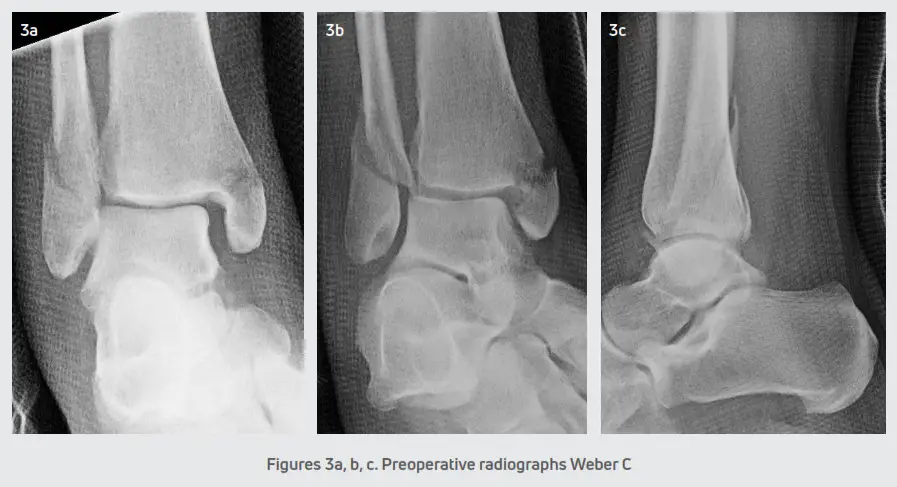

All the patients were seen at the senior author’s private practice for an evaluation. Patients were splinted and initially kept non-weight bearing until the scheduled date for surgery. Open reduction and internal fixation of the ankle fractures were performed within 1 and 2.5 weeks post-injury depending on the edema and condition of the soft tissue envelope at the initial presentation. Each patient received preoperative radiographs. (Figures 2 and 3) Also, additional radiographs were taken at postoperative visits typically at weeks 4, 8, and 12. During each postoperative appointment, the fracture sites were examined for clinical signs of healing.

The incisions were closed in a standard layered fashion and a sterile, compressive dressing was applied. All patients were immobilized with a posterior splint and were initially non-weight bearing. Patients were seen for the first postoperative visit within 5-6 days for a wound evaluation. A sterile dressing and posterior splint were reapplied and patients returned at two weeks for suture removal. The postoperative course consisted of non-weight bearing in a posterior splint for 2-3 weeks. In ankle fractures with a stable syndesmosis (Figure 4), patients were transitioned into a CAM boot at 3 weeks and began protected partial weight-bearing with physical therapy. After 6 weeks, patients were transitioned to a supportive athletic shoe with an ankle brace and the final follow-up was at 12 weeks. In ankle fractures that required syndesmotic repair (Figure 5), patients were transitioned into a CAM boot and began protected partial weight-bearing at approximately 8-10 weeks. Patients were progressed into normal shoe gear at 12 weeks and aggressive physical therapy. Patients were discharged at 4-6 months and followed up as needed.